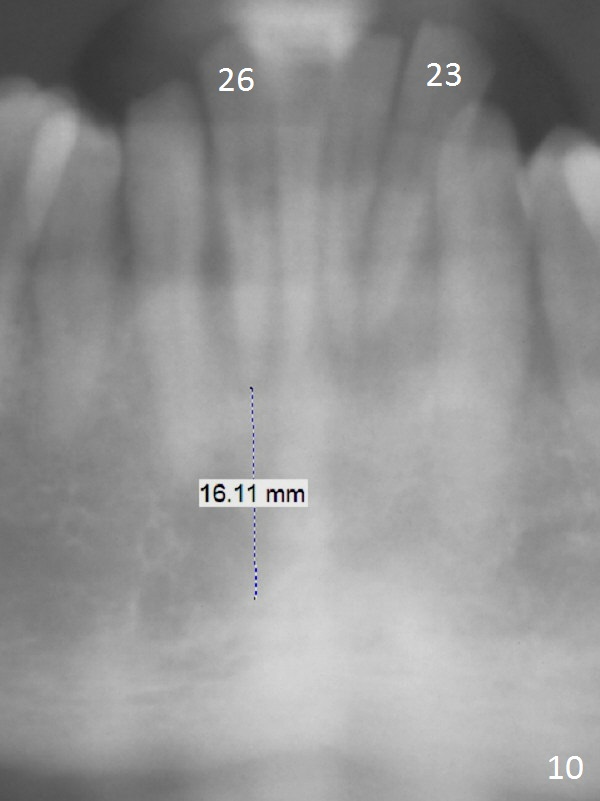

A 36-year-old man (ex-smoker) has advanced chronic periodontitis (Fig.1-5). His chief complaint is "I cannot chew on the right side now because of pain (Fig.1: #3 abscess <) and the bottom front teeth are loose (Fig.2,5: #23-26)". He has not masticated on the left side because of the mobile teeth. Due to finance, implants will be placed at #3,4 (Fig.12), 23 and 26 at the appointments of scaling & root planing.

Class II Division II malocclusion (Fig.2,6) will make it difficult to restore #23-26 implant-supported FPD. Although the teeth #7-10 may need to be replaced later (Fig.7,8), enameloplasty will be conducted for #7-10 (Fig.9 white area; Fig.12 black circles (gross reduction)) prior to #23-26 extraction and implant placement (Fig.10). To be flexible in restoration (angulation) and possible future hybrid denture, 2-piece narrow implants will be placed (3.0 or 3.3 mm) instead of 1-piece ones. In fact CBCT shows that the narrowest regular implant (3.8 mm) can be placed in the lower anterior region (Fig.13-15).